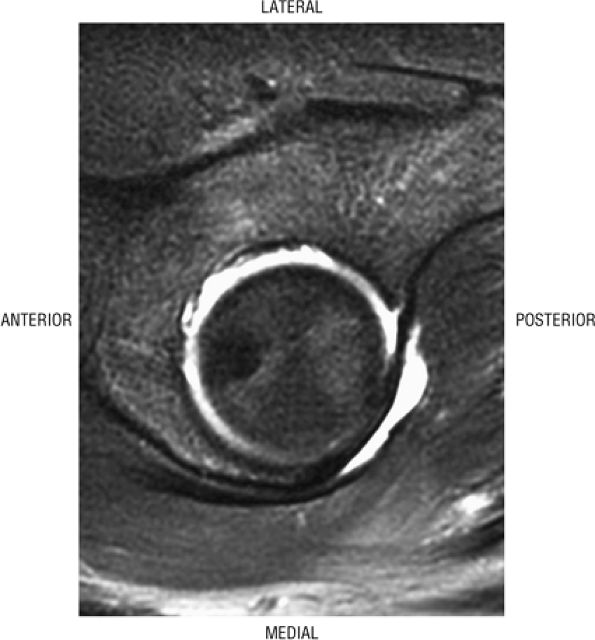

The hip musculature demonstrates intermediate signal intensity on T1-weighted images. The gluteal muscles—the gluteus medius laterally, the gluteus minimus deep, and the gluteus maximus posteriorly—can be differentiated from one another by high-signal-intensity fat along fascial divisions. The tensor fasciae latae muscle is seen anterior to the gluteus medius and is bordered anteriorly by subcutaneous fat. The iliopsoas muscle group is anterior to the femoral head in a 12-o—clock position. The sartorius muscle is the most anterior, and the rectus femoris is positioned between the more lateral tensor fasciae latae and the medial iliopsoas. The obturator internus muscle is visualized medial to the anterior and posterior acetabular columns.

The femoral head articular cartilage demonstrates intermediate signal intensity, and the anterior and posterior fibrocartilaginous acetabular labrum may also be identified at this level. The acetabular labrum is triangular, with the apex oriented laterally.